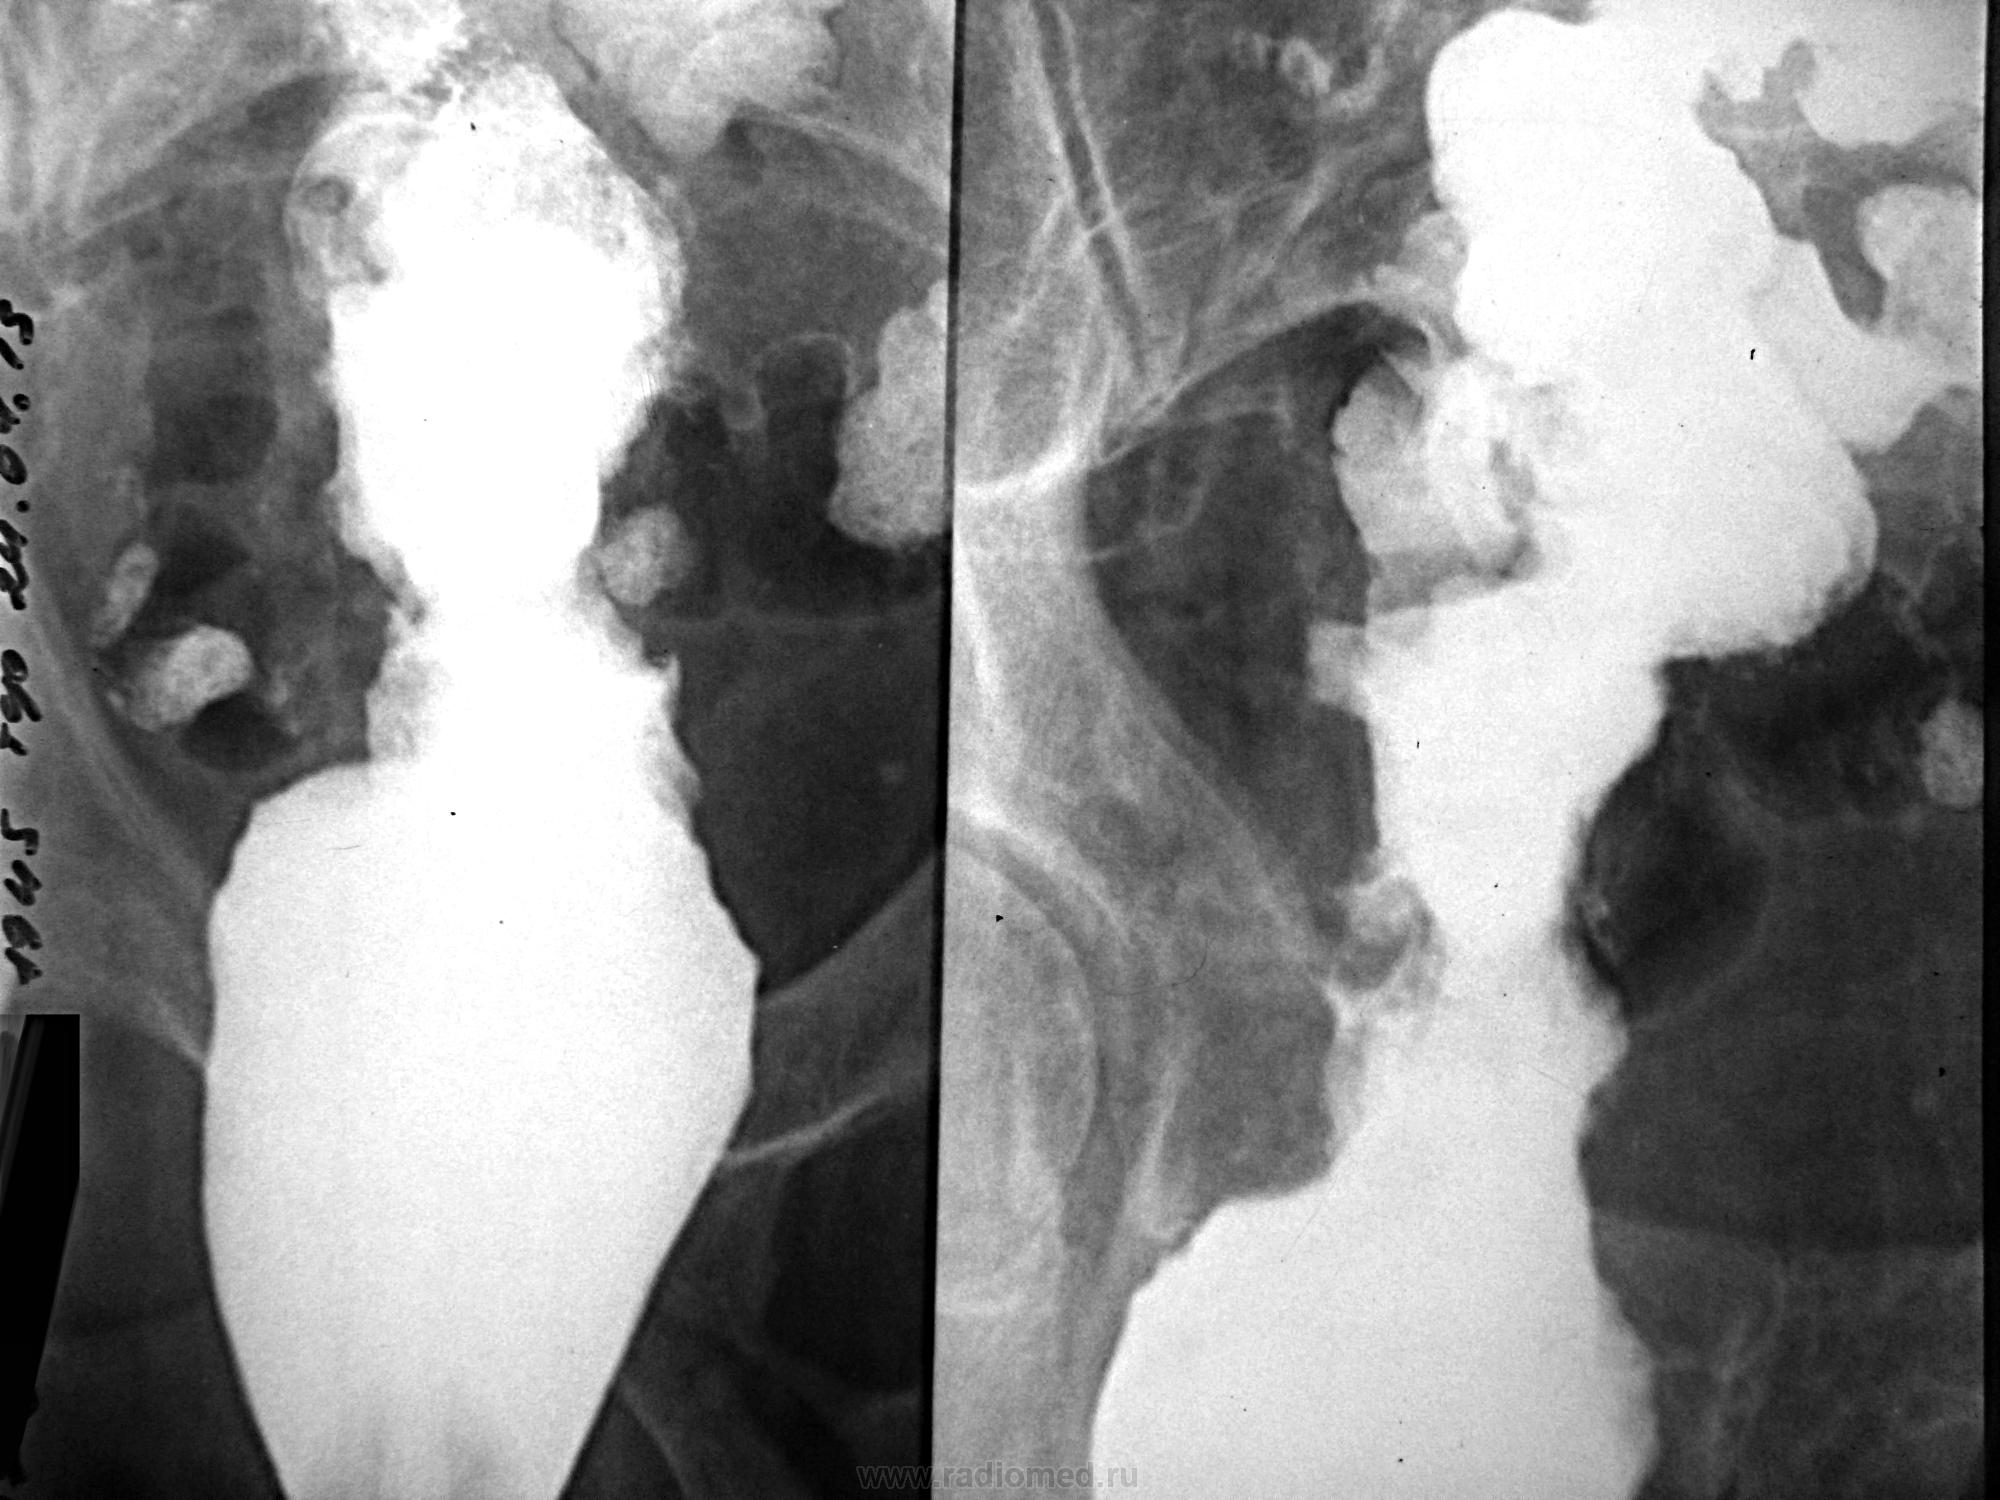

Пациент с жалобами на запоры. Ирригоскопия после RRS (тубус после 10 см не прошел).

Коллега, а обзорный снимок не делали и что написали по status loclis на RRS? Какое-то органическое поражение дистальных отделов толстой кишки с массивной циркулярной инфильтрацией и боковыми затёками  контраста ( рак ? болезнь Крона? неспецифический язвенный колит?)

Скорее рак, но может и лимфома.

Извините за молчание (уезжал). На RRS - циркулярная бугристая опухоль грязно-серого цвета. На гистологии - аденокарцинома. Насчет обзорного снимка - зачем? - выложены прицельные РГ.